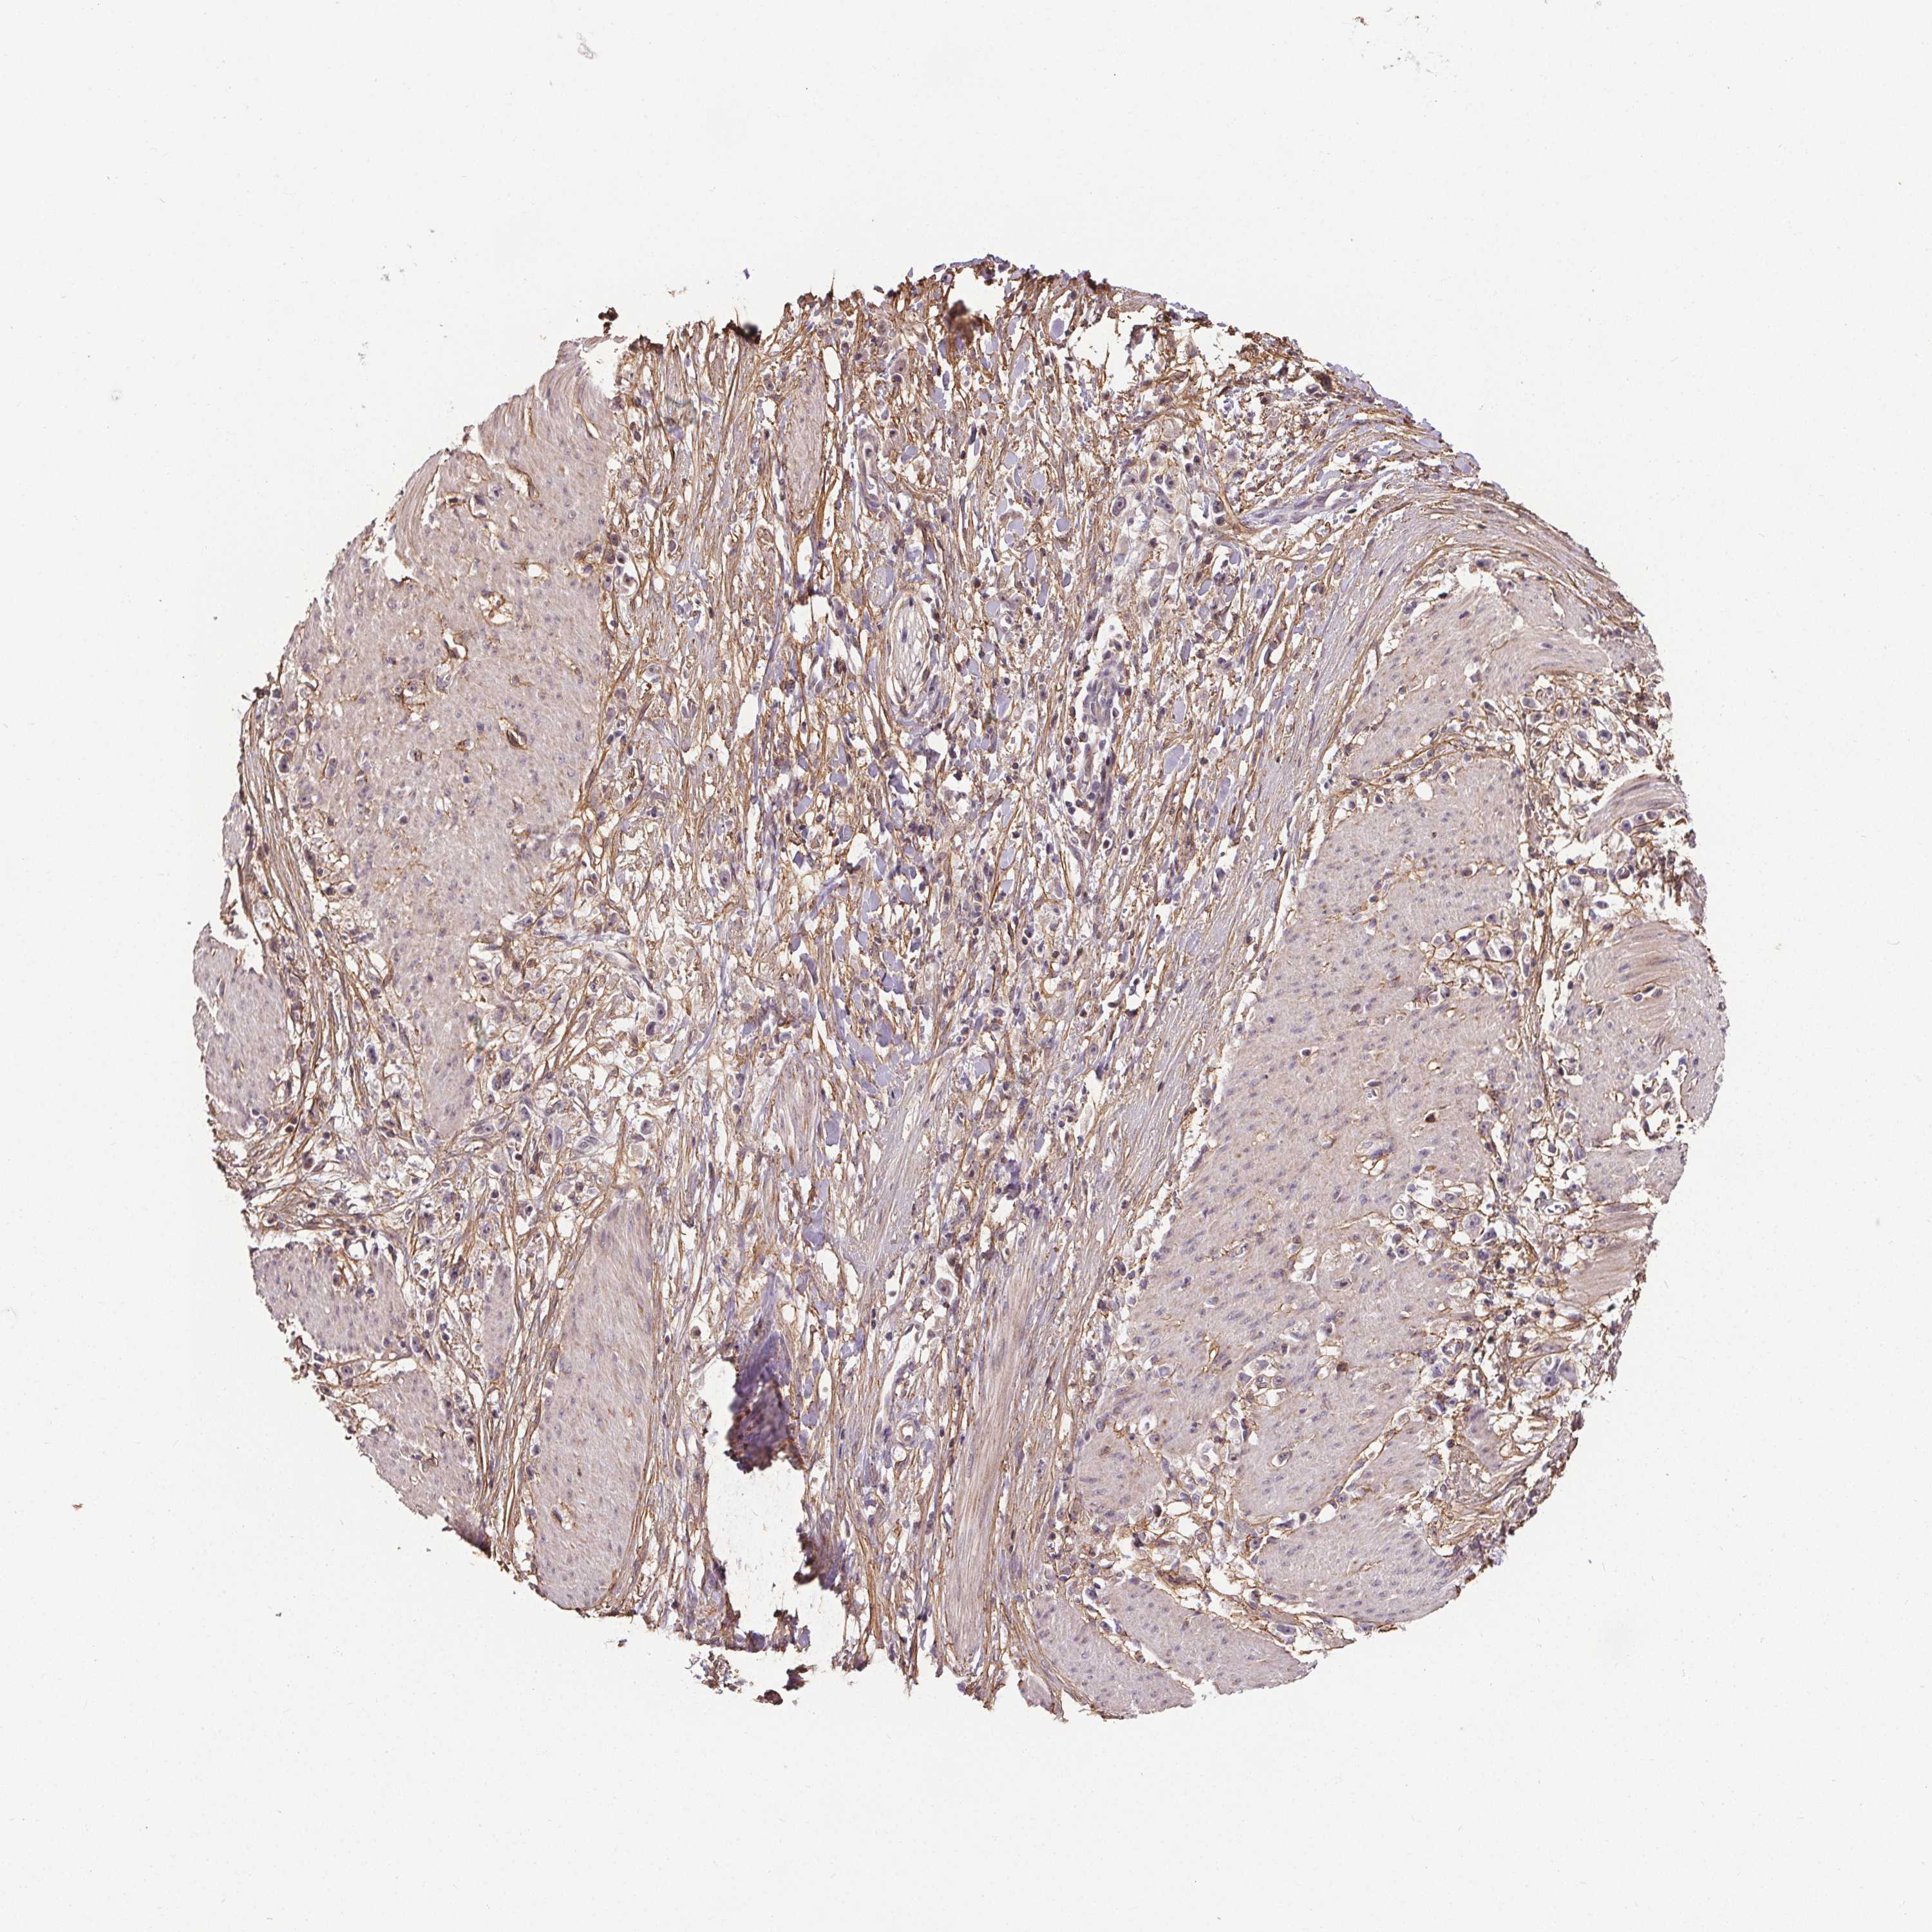

STOMACH CANCER - Protein expressioni

A mouse-over function shows sample information and annotation data. Click on an image to view it in a full screen mode. Samples can be filtered based on level of antibody staining by selecting one or several of the following categories: high, medium, low and not detected. The assay and annotation is described here.

Note that samples used for immunohistochemistry by the Human Protein Atlas do not correspond to samples in the TCGA dataset.

Antibody stainingi

Antibody staining in the annotated cell types in the current human tissue is reported as not detected, low, medium, or high, based on conventional immunohistochemistry profiling in selected tissues. This score is based on the combination of the staining intensity and fraction of stained cells.

Each image is clickable and will lead to virtual microscopy that enables deeper exploration of all samples and also displays staining intensity scores, fraction scores and subcellular localization as well as patient and tissue information for each sample.

Antibody HPA036891

Antibody HPA036892

Antibody HPA061498

Staining

High

Medium

Low

Not detected

Intensity

Strong

Moderate

Weak

Negative

Quantity

>75%

75%-25%

<25%

None

Location

Nuclear

Cytoplasmic/membranous

Cytoplasmic/membranous,nuclear

Adenocarcinoma, NOS